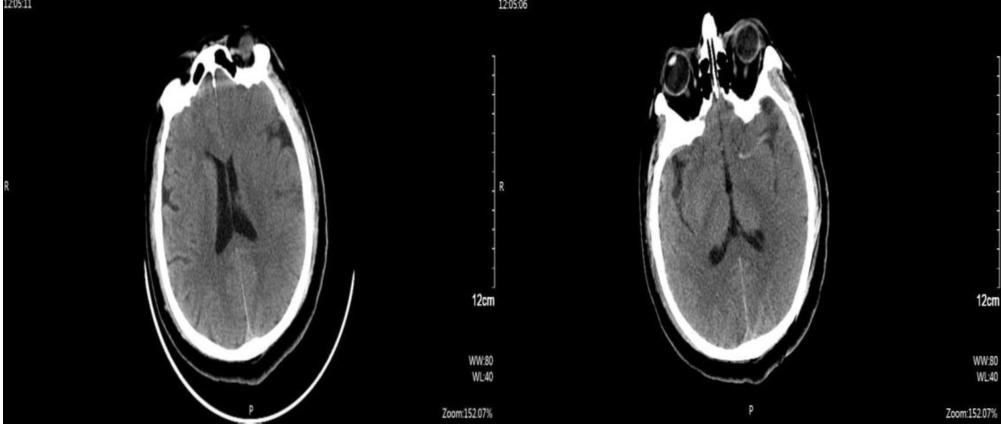

急诊头部CT:左侧脑组织密度减低,水肿,脑沟、脑回变浅、脑室受压,左侧大脑中动脉高密度征。

入院CT